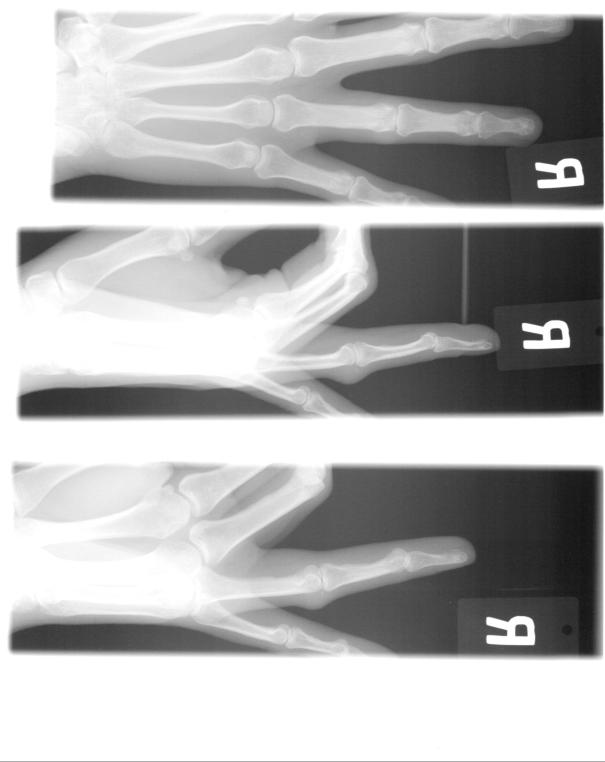

Sen var det dags för röntgen för att se om fingret var brutet. Det visade sig att det lossnat en liten, liten flisa vi den första leden på fingret. Dock behövde jag inte gipsas som tur var, utan han tejpade ihop fingret med långfingret istället. Om inte svullnaden och värken gått ner betydligt om två veckor så måste jag dit igen, annars ska det vara helt läkt om fyra veckor. En kul grej: när vi gick därifrån fick vi med oss röntgenplåtarna på en cd-skiva! Så om någon vill se hur mitt finger ser ut så har ni det här (det är alltså röntgat efter att han dragit fingret i rätt läge så det ser inte läskigt ut:

Man kan se som en liten kula där leden svullnat, men jag kan inte upptäcka den lösa flisan hur mycket jag än tittar så den måste verkligen varit liten!